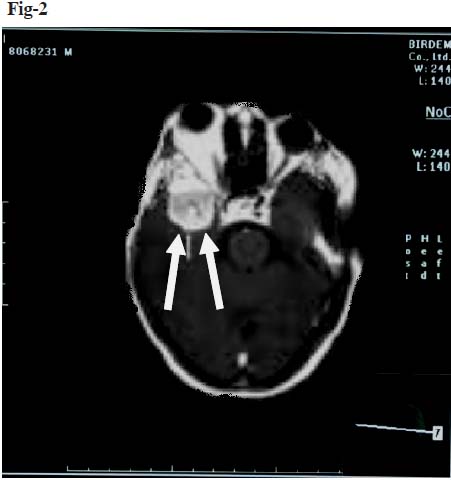

A 42 year old female presented with history of gradual protrusion of the right eye for two years with complete loss of vision of the same eye for the last two months. The patient was referred to Department of Radiology and Imaging, BIRDEM from the Department of Neurosurgery, BSMMU. She had history of itching of both upper and lower eyelids for one and half years and gradual dimness of vision of the right eye for last six months. Fundus examination of right eye revealed that there was temporal disc pallor with bulging of the optic disc. There was no motor or sensory in-coordination, gait deficit or any asymmetry in reflexes. She was mildly anemic. The biochemical investigations were unremarkable. Computerized tomography (CT) of the brain and orbit with and without contrast revealed iso-dense soft tissue mass in right infra temporal fossa along the lateral wall of the right orbital cavity displacing the right optic nerve to the left (Figure 1). The mass revealed strong homogenous enhancement. Bone window of CT showed hyperostosis and gross thickening with hazy margin of greater and lesser wings of the sphenoid bone, frontal process of zygomatic bone and adjacent part of squamus part of temporal bone on the right side. There was irregularity of inner table of the affected bones. CT findings suggested right sphenoidal meningioma with intraorbital, extracranial and infratemporal components. Thickening of right lateral and superior recti muscles were demonstrated. Polyostotic fibrous dysplasia was also suspected as differential diagnosis. MRI of the brain with orbit (T1 axial, sagittal and T2 axial) was done with and without gadolinium-DTPA scan. Irregular frank expansion and deformity of right sphenoidal wing, petro-temporo-zygomatic bone with intermediate signal intensity in T1WI and T2WI was demonstrated. There was strong contrast enhancement of the lesion (Figure 2). There was also linear thick nodular enhancement involving the dura overlying the right temporoparietal lobes. Right orbital canal and orbital fissure were narrowed with encroachment of right optic nerve. The finding was indicative of intraosseus meningioma.

Fig-1. CT of the brain and orbit showing iso-dense soft tissue mass in right infra temporal fossa along the lateral wall of the right orbital cavity displacing the right optic nerve to the left (black arrow). Bone window of CT showed hyperostosis and gross thickening with hazy margin of greater and lesser wings of the sphenoid bone (white arrow).